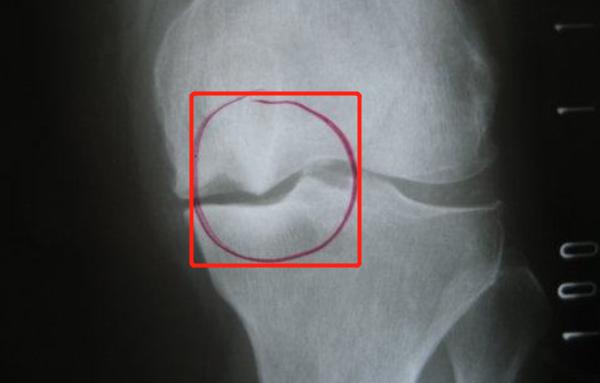

人体关节内有一块软骨,它负责骨头间的缓冲和承压,但随着人年龄的增长,软骨会出现磨损(尤其是膝关节),骨头与骨头之间就会"硬碰硬",刺激骨头表面的骨膜增生,慢慢就会形成骨赘。当患者拍摄x光时,能在x光片上看到骨骼有尖尖的突起样表现。

x光片下的骨赘